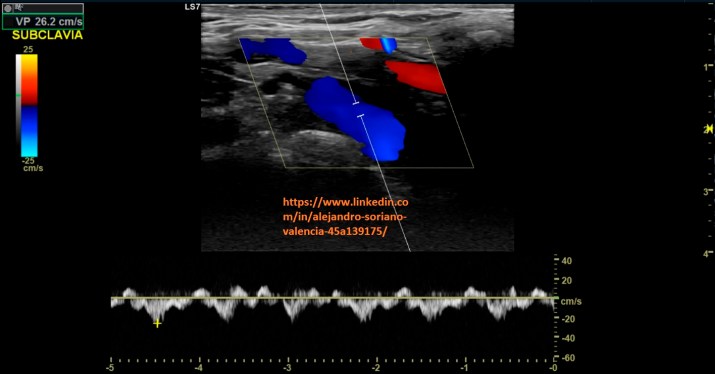

Como vimos en el post nº 105 las venas tienen un patrón monofásico. Pues

bien, aquí tenemos dos excepciones, y es que, nos encontraremos con un

flujo pulsátil en las venas yugular interna y subclavia.

will become infraclavicular. It is a vessel with very difficult access, so we are not able to make transversal cuts and we will not be able to compress properly. As we saw in post no. 105, the veins have a monophasic pattern. Well, here we have two exceptions, and that is that, we will find a pulsating flow in the internal jugular and subclavian veins.

3. Subclavia longitudinal.